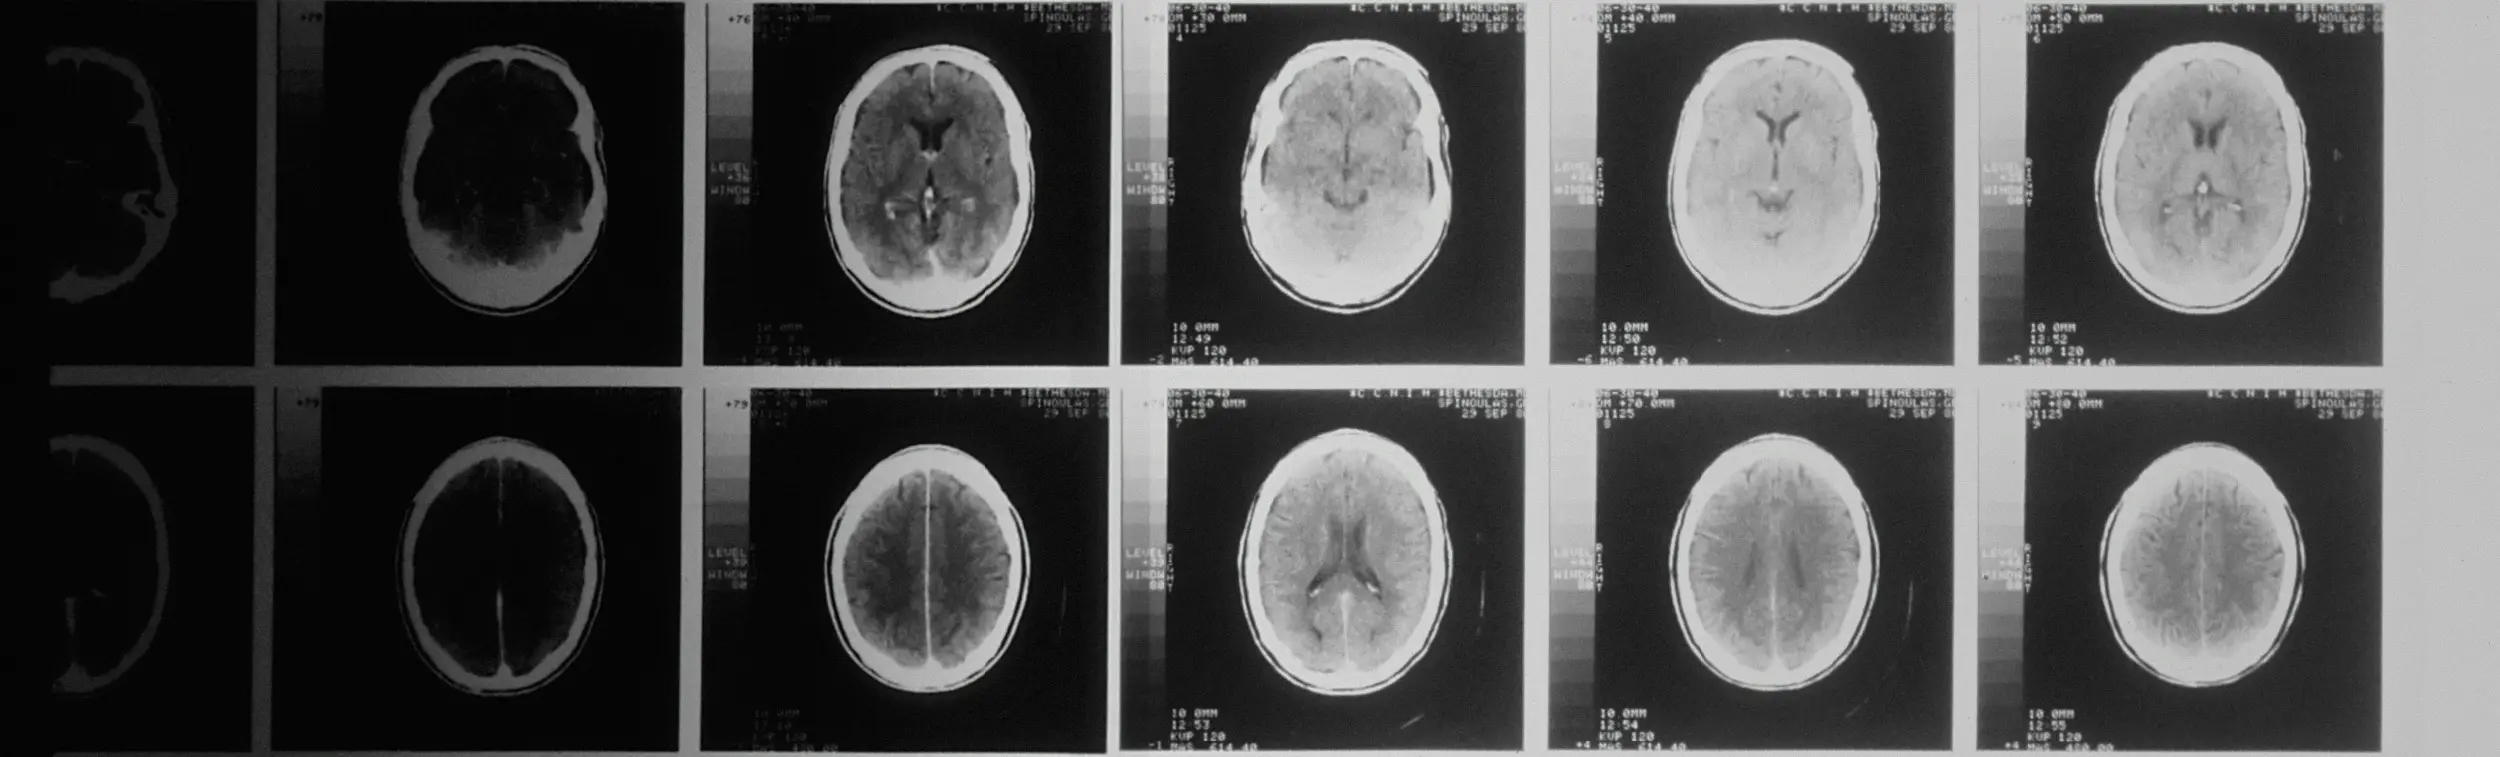

Une radiographie de la tête prise par un scanner assisté par ordinateur.